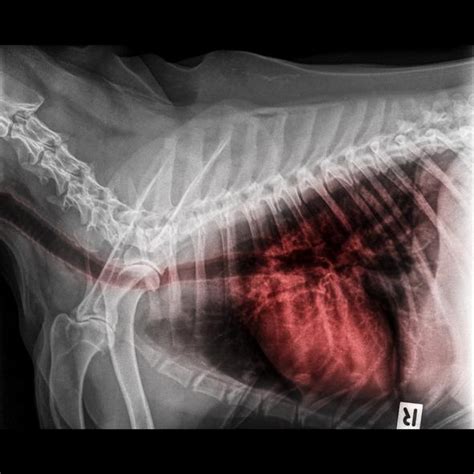

A chest X-ray is a common imaging test used to visualize the lungs and heart, revealing fluid accumulation and any structural abnormalities. An electrocardiogram (ECG) records the electrical activity of your heart, helping to identify any heart-related issues that might be contributing to the edema. Blood tests can measure oxygen and carbon dioxide levels in your blood, as well as assess kidney function and look for signs of infection. A B-type natriuretic peptide (BNP) blood test can help determine if heart failure is the cause of the pulmonary edema. In some cases, an echocardiogram (ultrasound of the heart) might be performed to evaluate the heart’s structure and function. These diagnostic tools help doctors accurately diagnose pulmonary edema and develop an appropriate treatment plan.